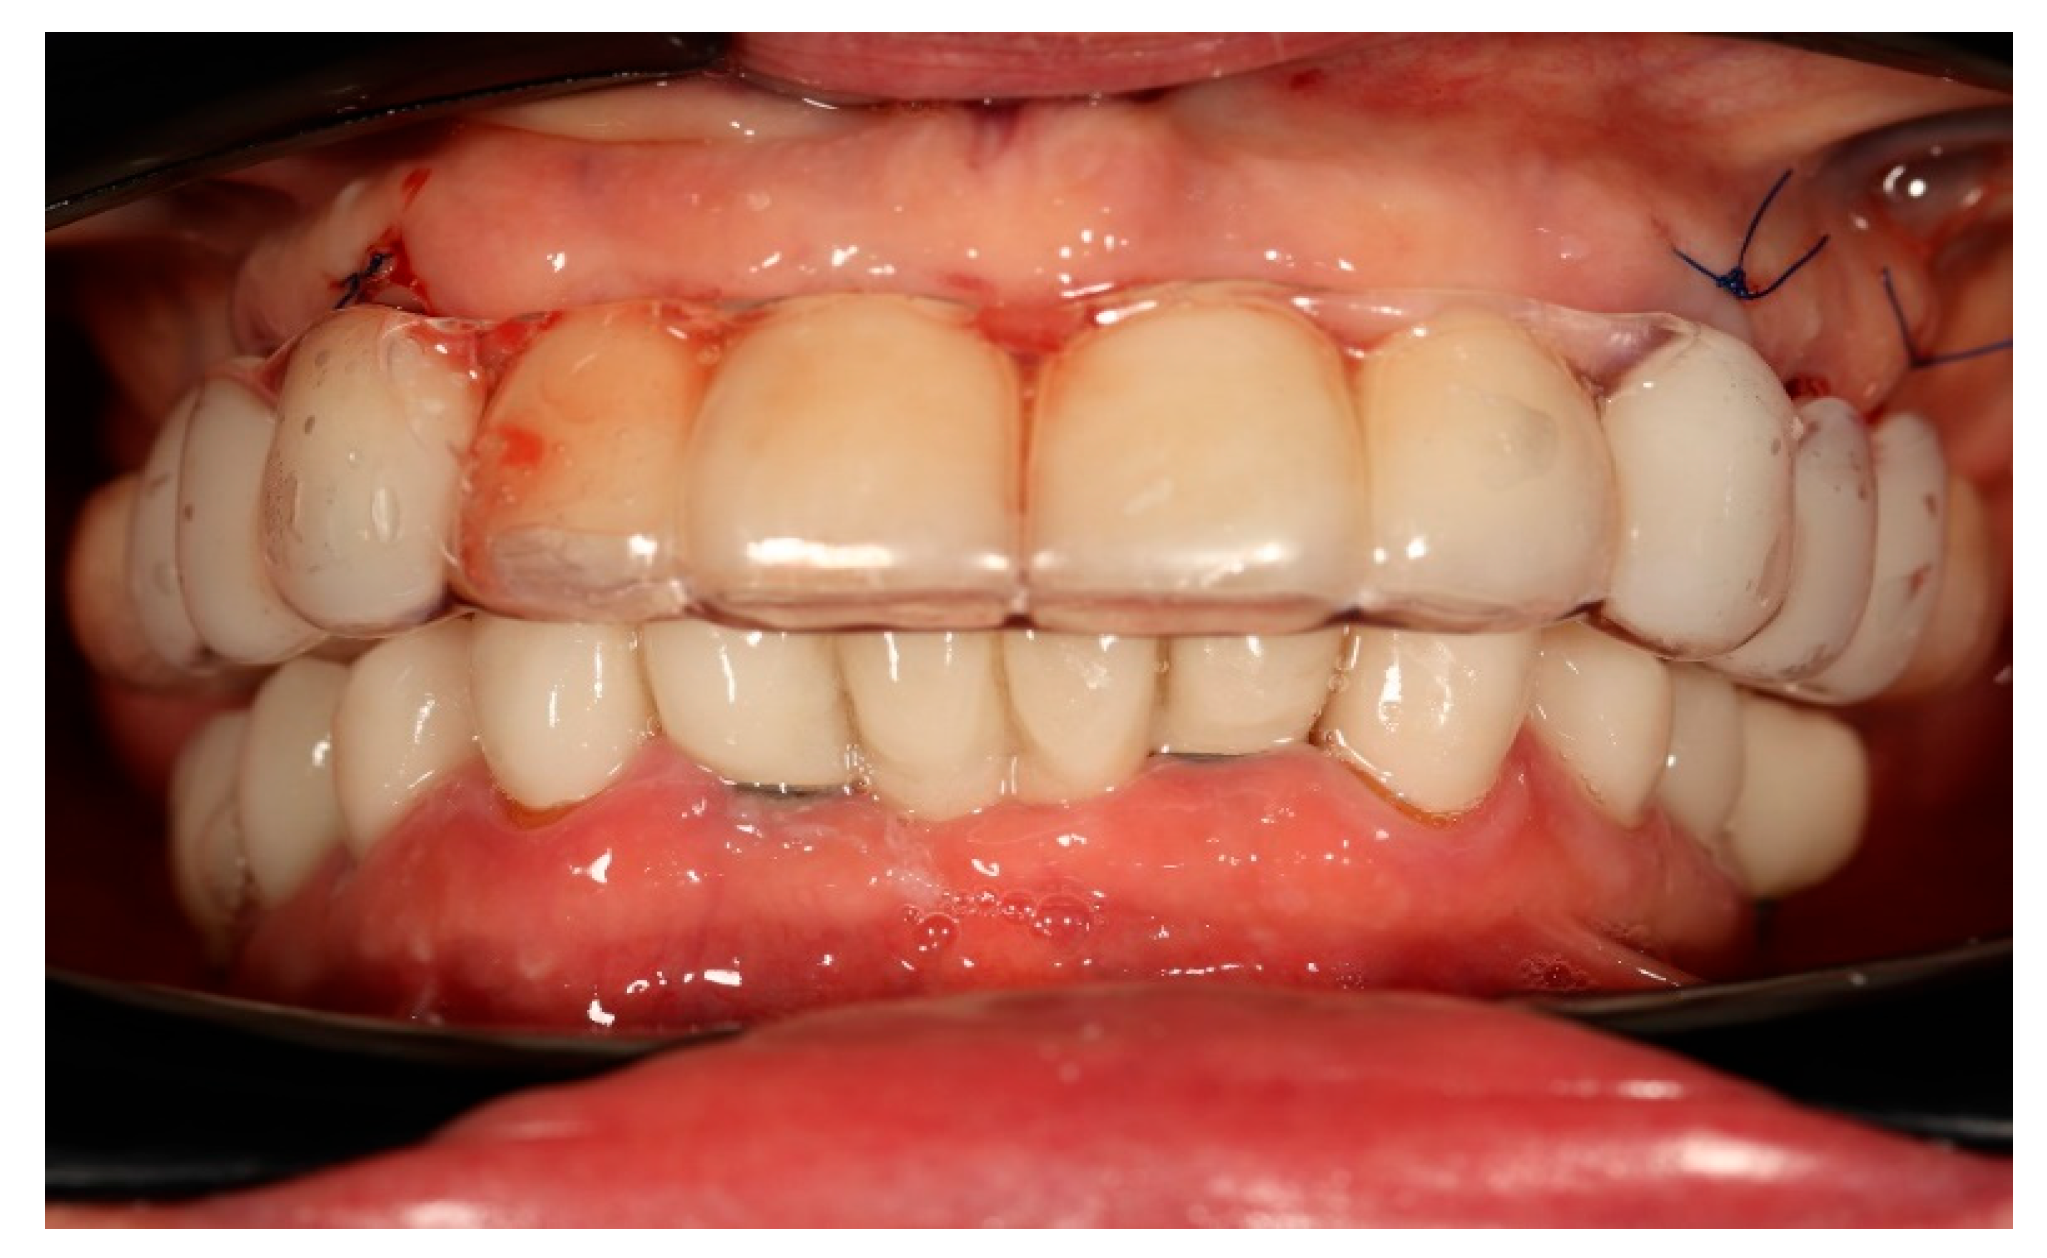

Finally, the prosthesis was delivered by fixing to the multi-unit abutments with screws. Clinical adjustments were performed to ensure perfect fit, occlusion, phonetics, and aesthetics. The patient reported immediate improvement in comfort and satisfaction compared to the acrylic splint (Figure 9 and Figure 10).

Figure 10. Digitally planned, 3D-printed full-arch provisional restoration after the healing phase and fixed to the multi-unit abutments screws, shown in situ (front view).